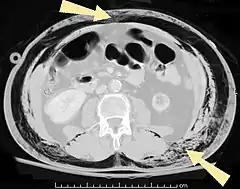

Pneumatosis is the abnormal presence of air or other gas within tissues.[1]

In the lungs, emphysema involves enlargement of the distal airspaces,[2] and is a major feature of chronic obstructive pulmonary disease (COPD). Other pneumatoses in the lungs are focal (localized) blebs and bullae, pulmonary cysts and cavities.

Pneumoperitoneum (or peritoneal emphysema) is air or gas in the abdominal cavity, and is most commonly caused by gastrointestinal perforation, often the result of surgery.

Abdominal

- Pneumoperitoneum (or peritoneal emphysema), air or gas in the abdominal cavity. The most common cause is a perforated abdominal viscus, generally a perforated peptic ulcer, although any part of the bowel may perforate from a benign ulcer, tumor or abdominal trauma.

- Pneumatosis intestinalis, air or gas cysts in the bowel wall

- Gastric pneumatosis (or gastric emphysema) is air or gas cysts in the stomach wall[6]